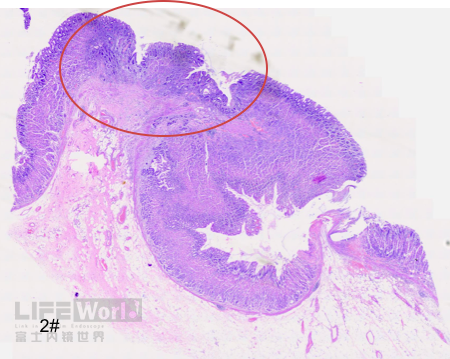

HE染色:2号切片示中分化腺癌,6号切片示高级别上皮内瘤变,局灶癌变。

这是2号切片,病变位于一条皱襞顶端。

病变处(红圈内)可见不规则的腺管状结构,部分呈筛网状。图中可以看出,病灶间可见相对正常的胃底腺结构。图片中最深的病灶已经侵及粘膜肌层。

病变处细胞异型性明显。病变内部可见多处扩张的腺管,内部可见坏死碎片。对应胃镜图片上的白色球状物。

此为病变最深的地方,癌变的腺管侵及粘膜肌层。